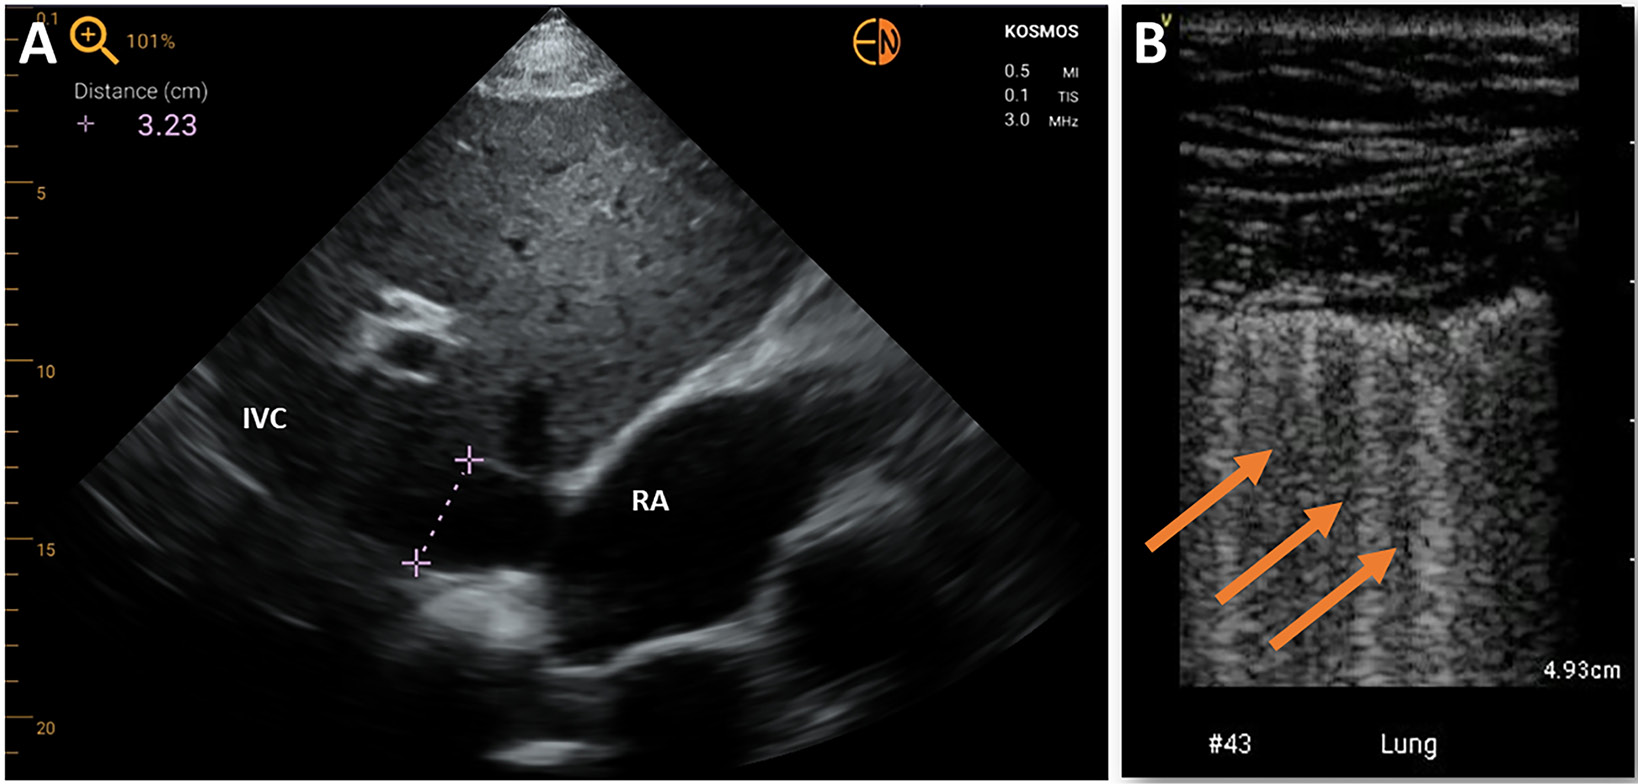

Several studies confirmed the feasibility of HUDs in assessing the width and collapsibility of the inferior vena cava (IVC) parameters used for estimating right atrial filling pressures, also in the setting of critical care unit. It is worth noting that in few studies, HUD operators were trained nurses.17, 18, 19 The presence of left atrium (LA) dilatation as a marker of increased LA pressures was proposed as one of the parameters to be evaluated in critically ill patients when performing their initial assessment.20

The HUD-performed lung ultrasonography became a particularly interesting diagnostic option in the time of COVID-19 pandemic.27, 28 Besides the identification of pleural effusion or subpleural consolidations, brief ultrasonographic assessment of “lung comets” allows the estimation of the level of congestion, which is vital in patients with heart failure (HF) (Figure 5).29